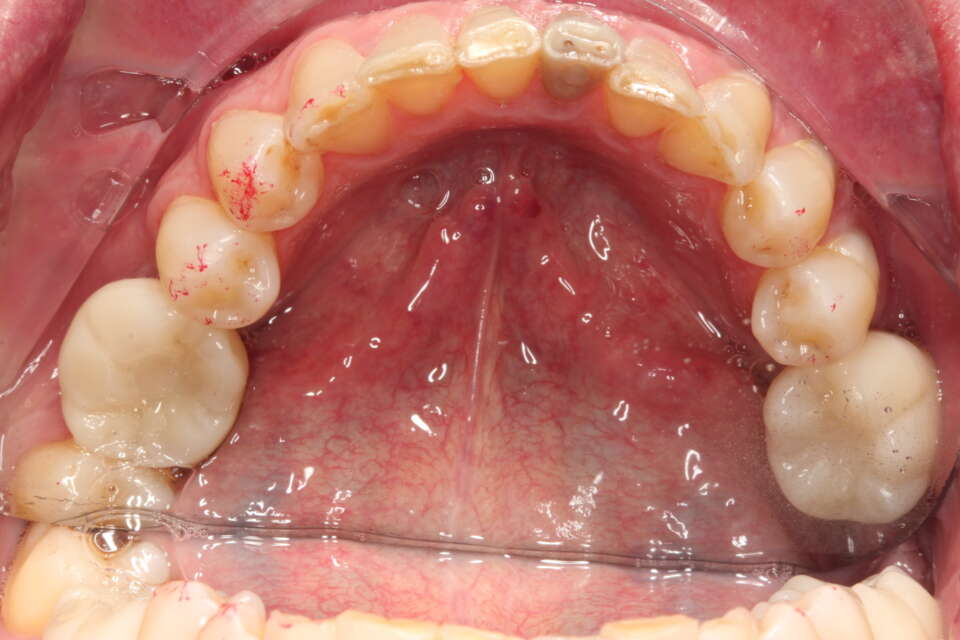

IMG 7536

The occlusal or birds eye view